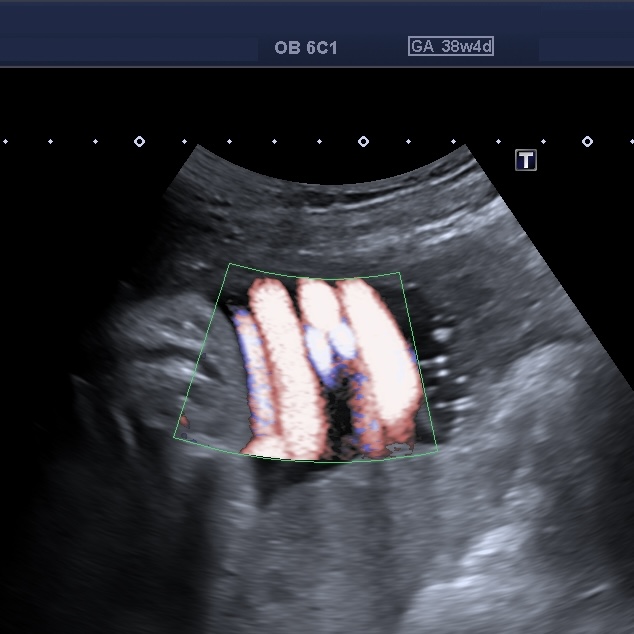

Se presenta el caso de una paciente primigesta, cursando un embarazo de 38 semanas de gestación, sin antecedentes de relevancia. Acude a la consulta para realizar una ecografía obstétrica con Doppler obstétrico. Refiere que, de mantenerse condiciones obstétricas favorables, se planificará un parto domiciliario. Hallazgos ecográficos: ? Feto único vivo, en presentación cefálica. ? Biometría acorde a la edad gestacional. ? Líquido amniótico dentro de parámetros normales. ? Placenta normoinserta. ? Doppler obstétrico dentro de rangos normales en todos los trayectos estudiados. A nivel del cuello fetal se observa las siguientes imágenes: Ante este hallazgo ecográfico usted: A) Interpreta doble circular de cordón y no la describe en el informe, ya que su presencia antenatal no modifica la conducta obstétrica ni predice por sí sola resultados adversos. B) Describe la doble circular de cordón umbilical como hallazgo ecográfico objetivo, especificando método diagnóstico, sin emitir recomendaciones obstétricas adicionales. C) Describe el hallazgo como circular de cordón múltiple e indica en el informe sugerencia de finalización institucional del embarazo debido al potencial riesgo intraparto.